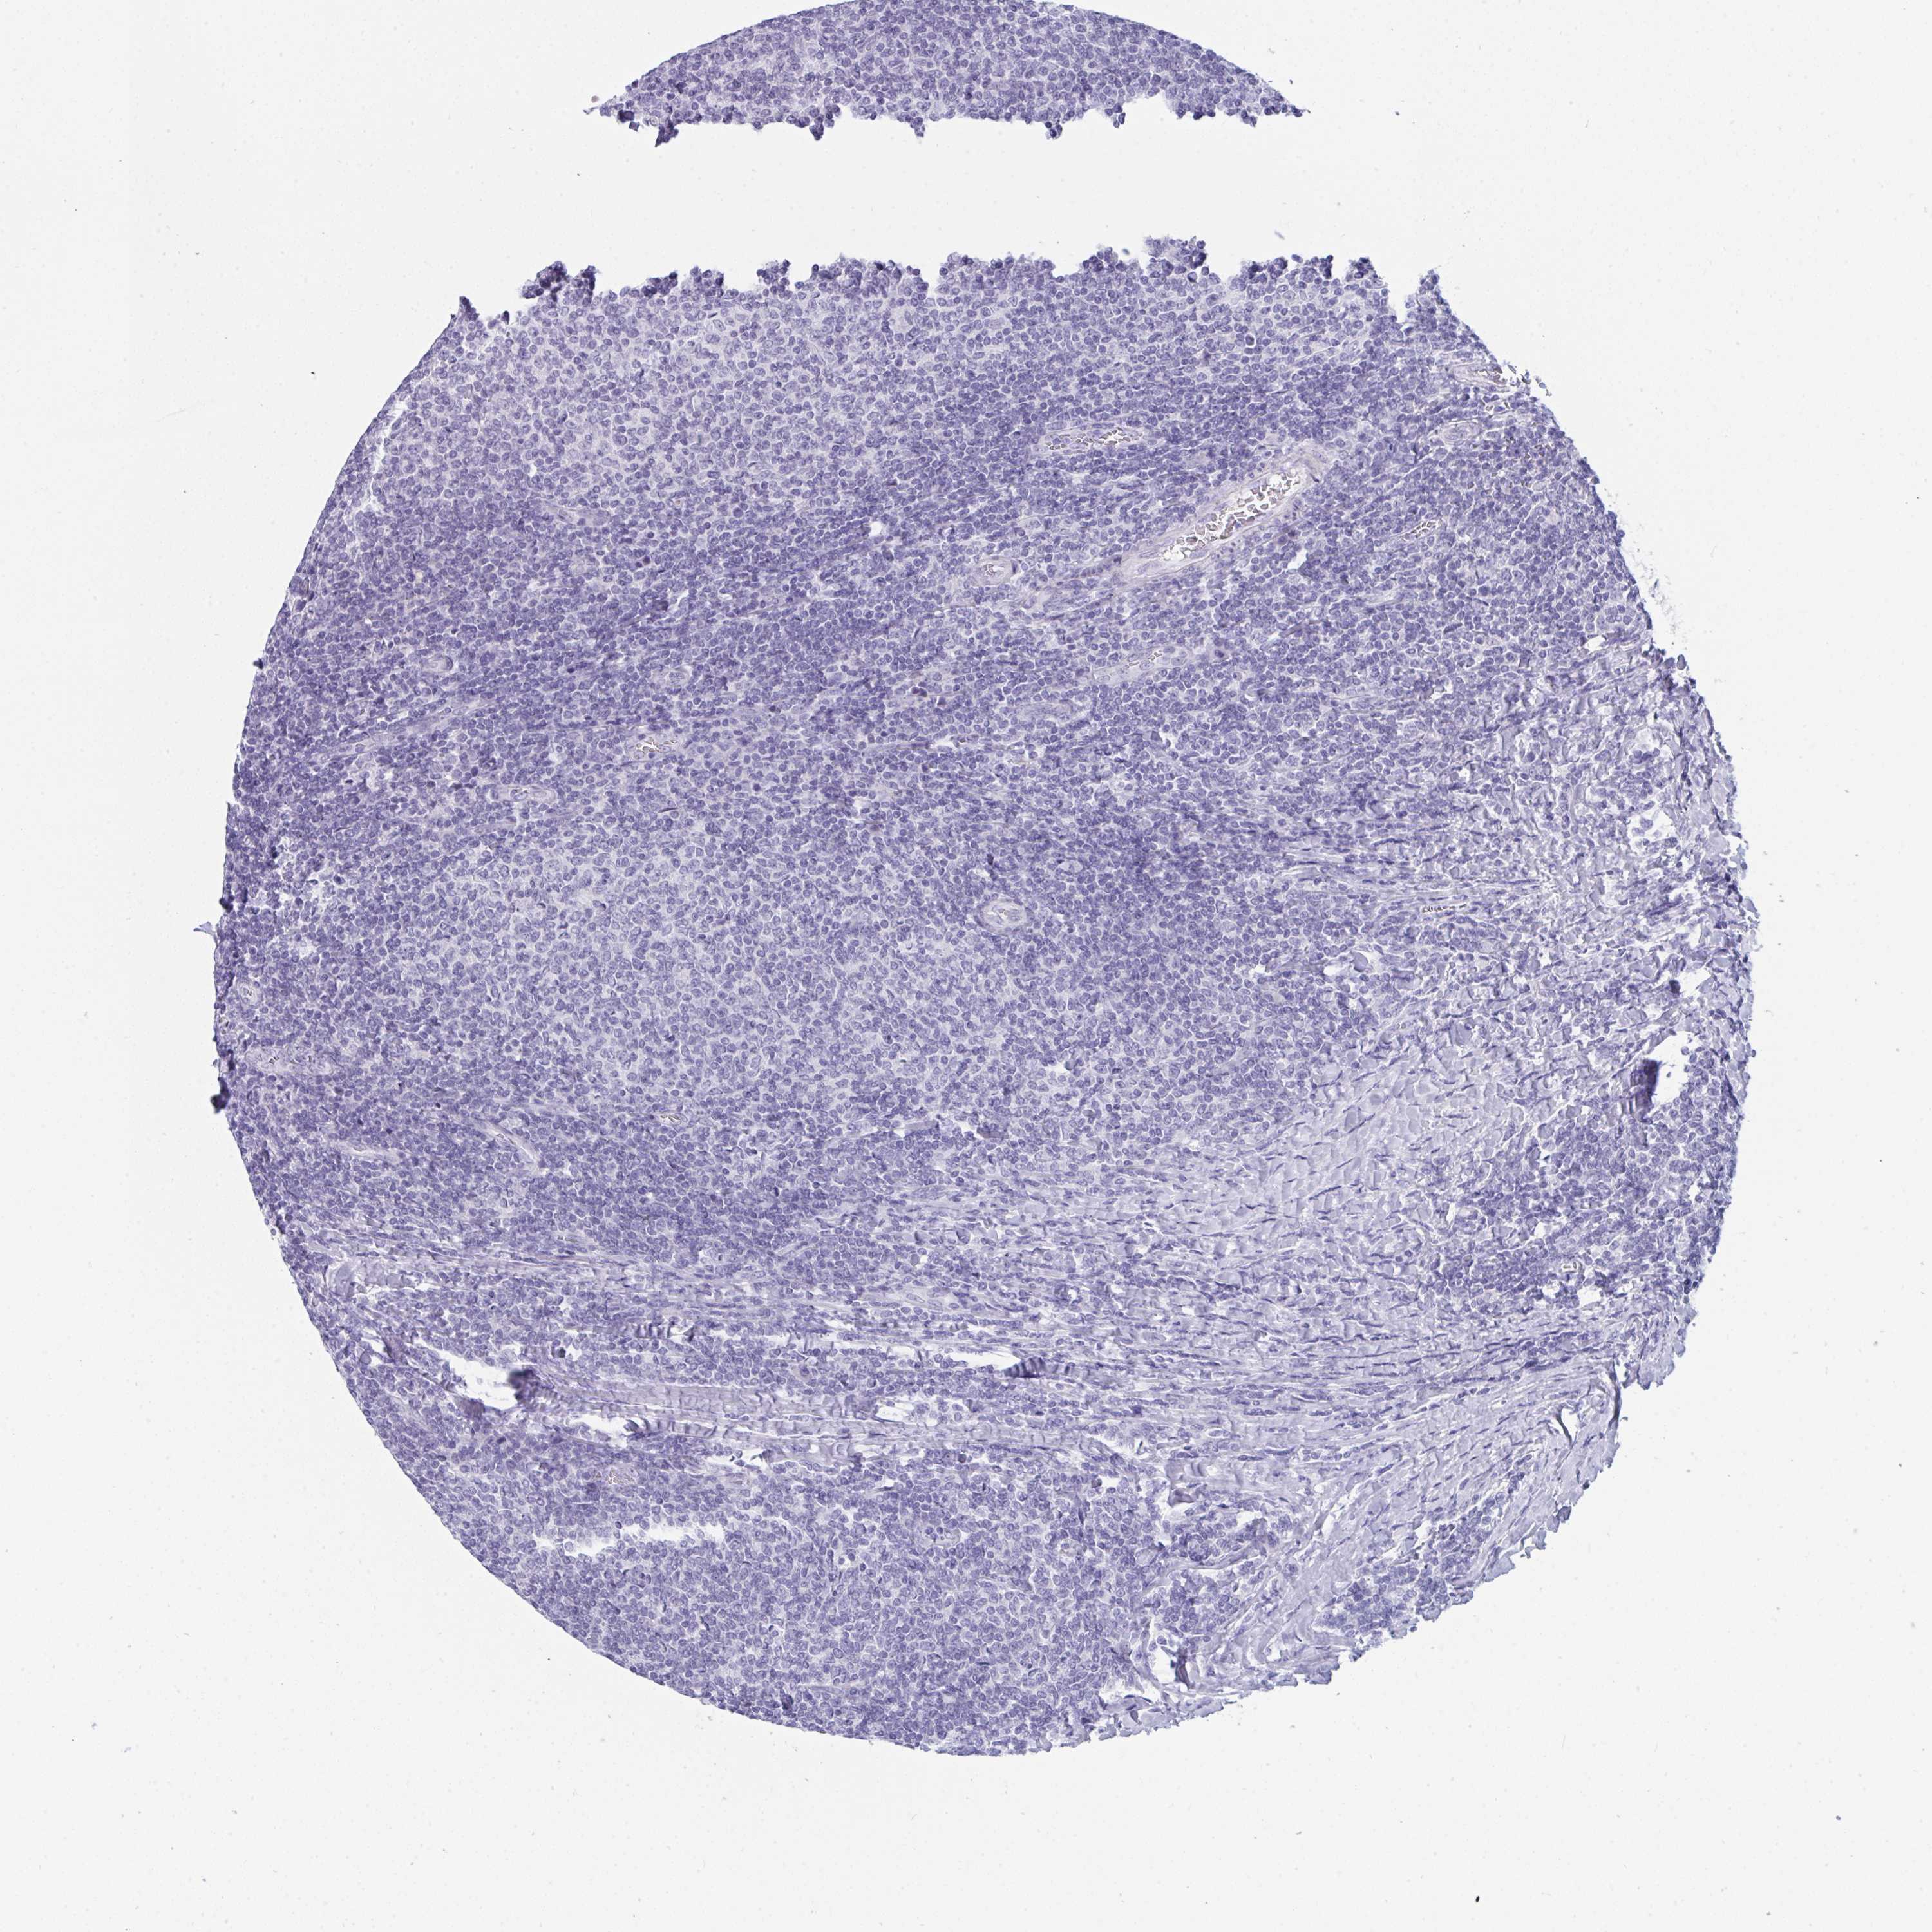

CANCER LYMPHOMA Show tissue menu

LYMPHOMA - Protein expressioni

A mouse-over function shows sample information and annotation data. Click on an image to view it in a full screen mode. Samples can be filtered based on level of antibody staining by selecting one or several of the following categories: high, medium, low and not detected. The assay and annotation is described here.

Each image is clickable and will lead to virtual microscopy that enables deeper exploration of all samples and also displays staining intensity scores, fraction scores and subcellular localization as well as patient and tissue information for each sample.

Antibody HPA059555

Staining

High

Medium

Low

Not detected

Intensity

Strong

Moderate

Weak

Negative

Quantity

>75%

75%-25%

<25%

None

Location

Nuclear

Cytoplasmic/membranous

Cytoplasmic/membranous,nuclear

Malignant lymphoma, non-Hodgkin's type, Low grade

Malignant lymphoma, non-Hodgkin's type, High grade

Hodgkin's disease, NOS